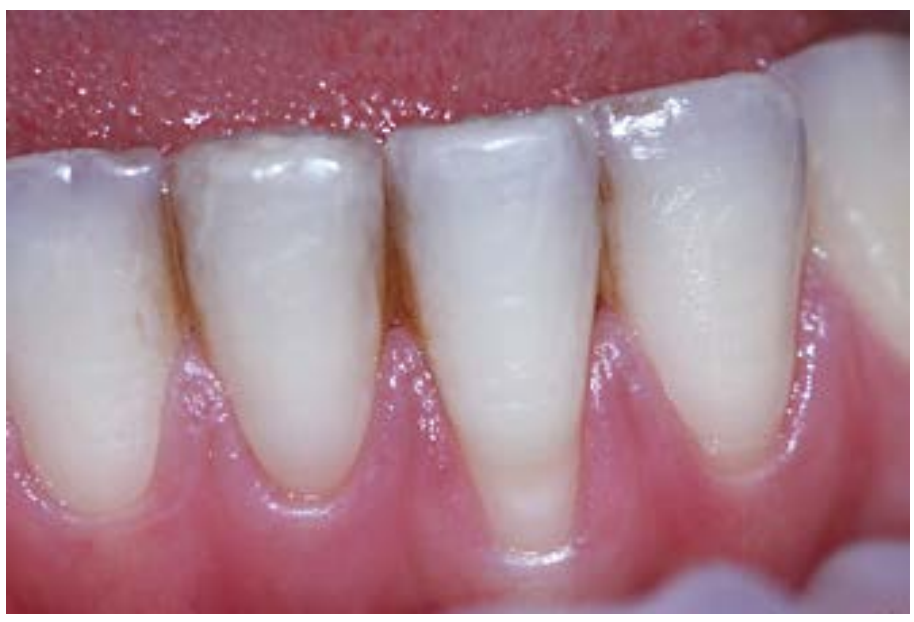

Рис. 6. Рецессия в области зуба 3.1, возникшая в процессе ортодонтического лечения

. В этом возрасте не наблюдали самопроизвольного устранения РД во фронтальном отделе верхнего зубного ряда. Чтобы не усугублять этот дефект и снизить натяжение мягких тканей пародонта и уменьшить размер зубов при макродентии проводили апроксимальную редукцию эмали. Однако при перемещении нижних резцов из лингвальной позиции вестибулярно у 2 пациентов наблюдали появление и у 1 углубление РД. Это осложнение ортодонтического лечения устраняли пластикой десны в ретенционном периоде (рис. 6, 7).